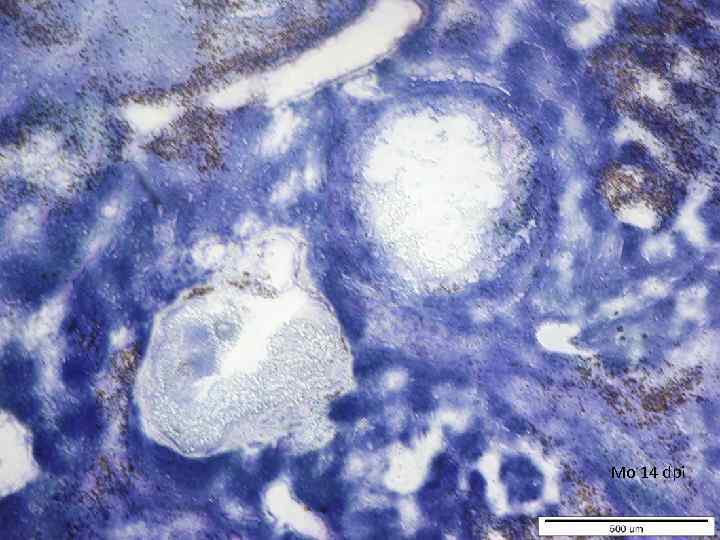

Mo 14 dpi

Mo 14 dpi